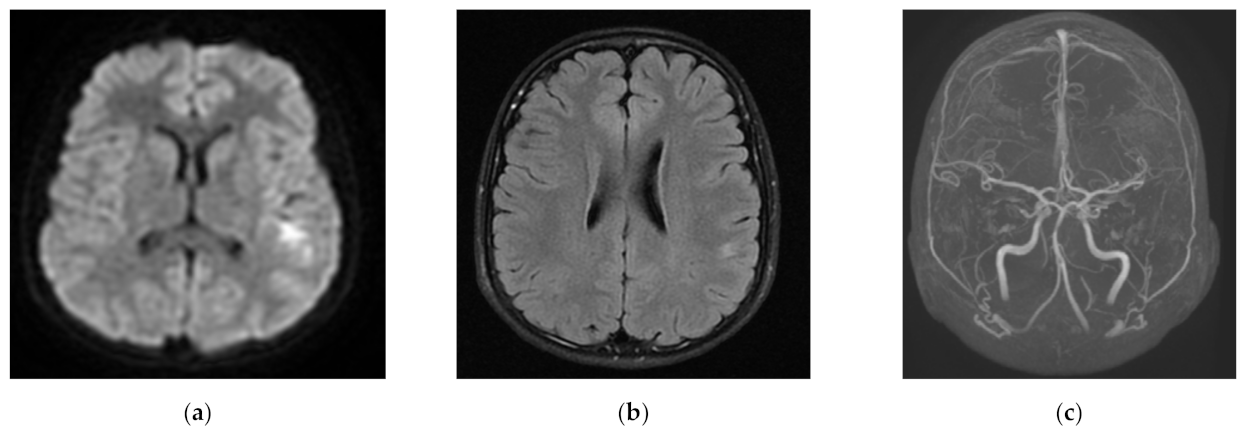

3.2. CT and MRI Reports